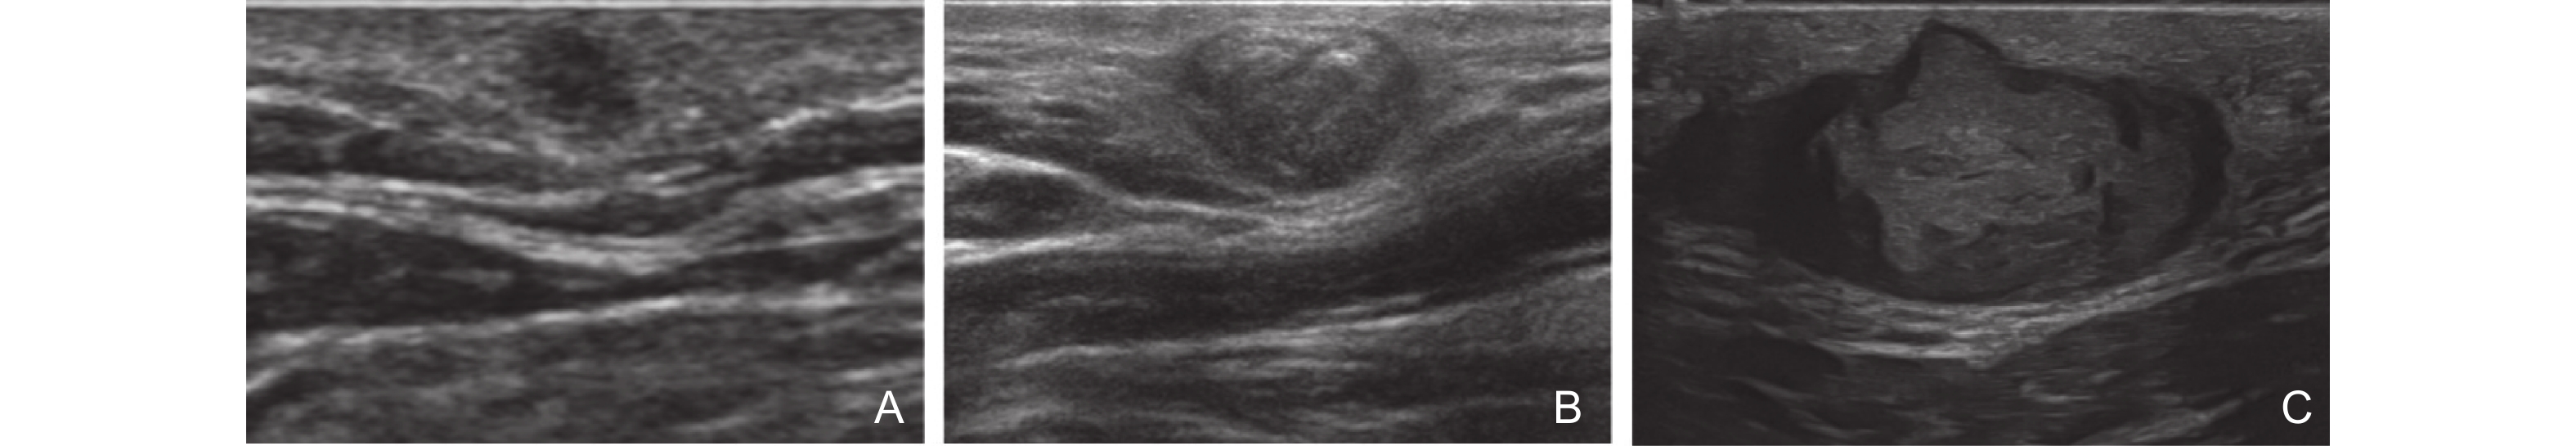

Figure 3

Clinical [47] and ultrasound manifestations of port-wine stains. (A) Pink type of PWS; (B) Purple type of PWS; (C) Thickening type of PWS; (D) Comparison of gray-scale ultrasound between the PWS lesion and the healthy side; (E) The blood flow signal at the lesion site of PWS increases."

| [47] | Xiang Xi , Zhang Lingyan , Zhong Lin , Gao Yi , Qiu Li . Multimodal ultrasound manifestations of port-wine stains and their application in efficacy assessment of photodynamic therapy. Chinese Journal of Dermatology 2024; 57: 801-806 |